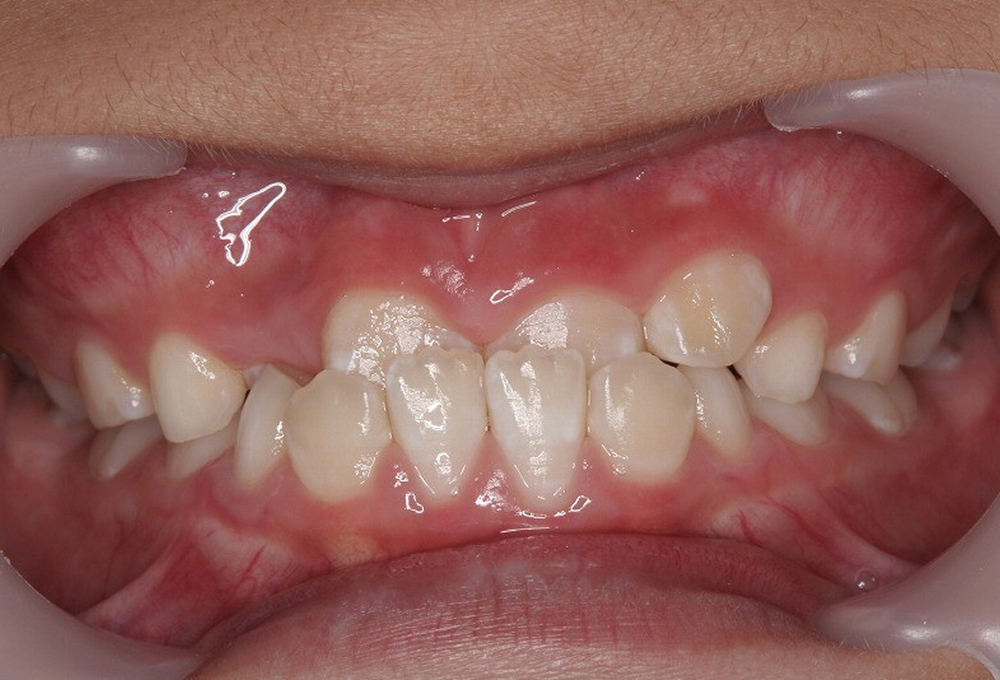

①術前 開咬